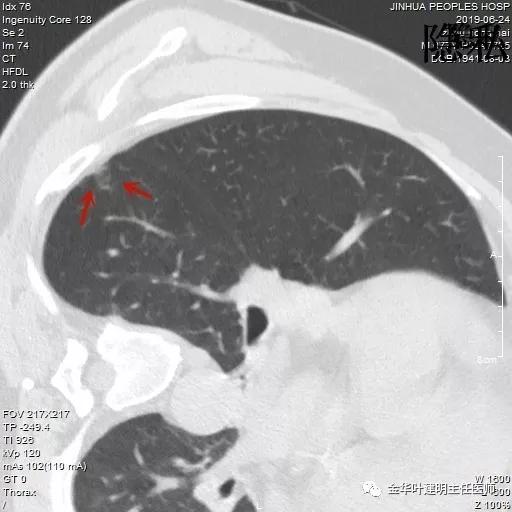

金华的周某,今年已经78岁了,上个月底单位退休人员体检,查出他的右肺有一结节,结果出来后,这个月通知他到胸外科复诊。因为是我的亲戚,便直接找到了我,我从电脑里调出他的CT片,如下所示:

可见其右下叶有一空腔性病灶,壁薄,病灶下方见到实性密度的成份。我们看过目前的片子后,马上想到的是此病灶以前有没有,对比是非常重要的。调出之前片子: